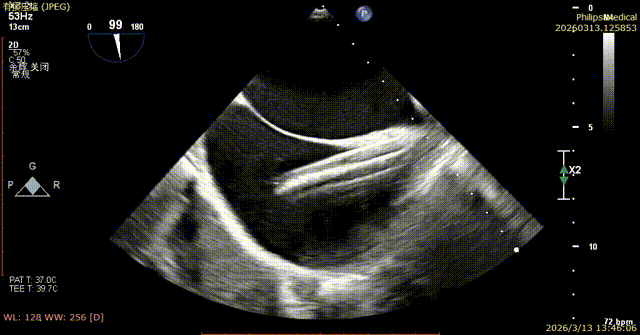

Transesophageal echocardiography upon admission showed regurgitant jets at the anteroseptal and central regions.

1. The first 14T device was positioned under the mid-esophageal bicaval view on TEE, and the tip of the delivery catheter was observed to point to the posterior-septal commissure of the tricuspid valve using 3D mode.

2. Under 3D mode switched to MPR-MultiVue mode, the trajectory was adjusted to anchor the tricuspid annulus.